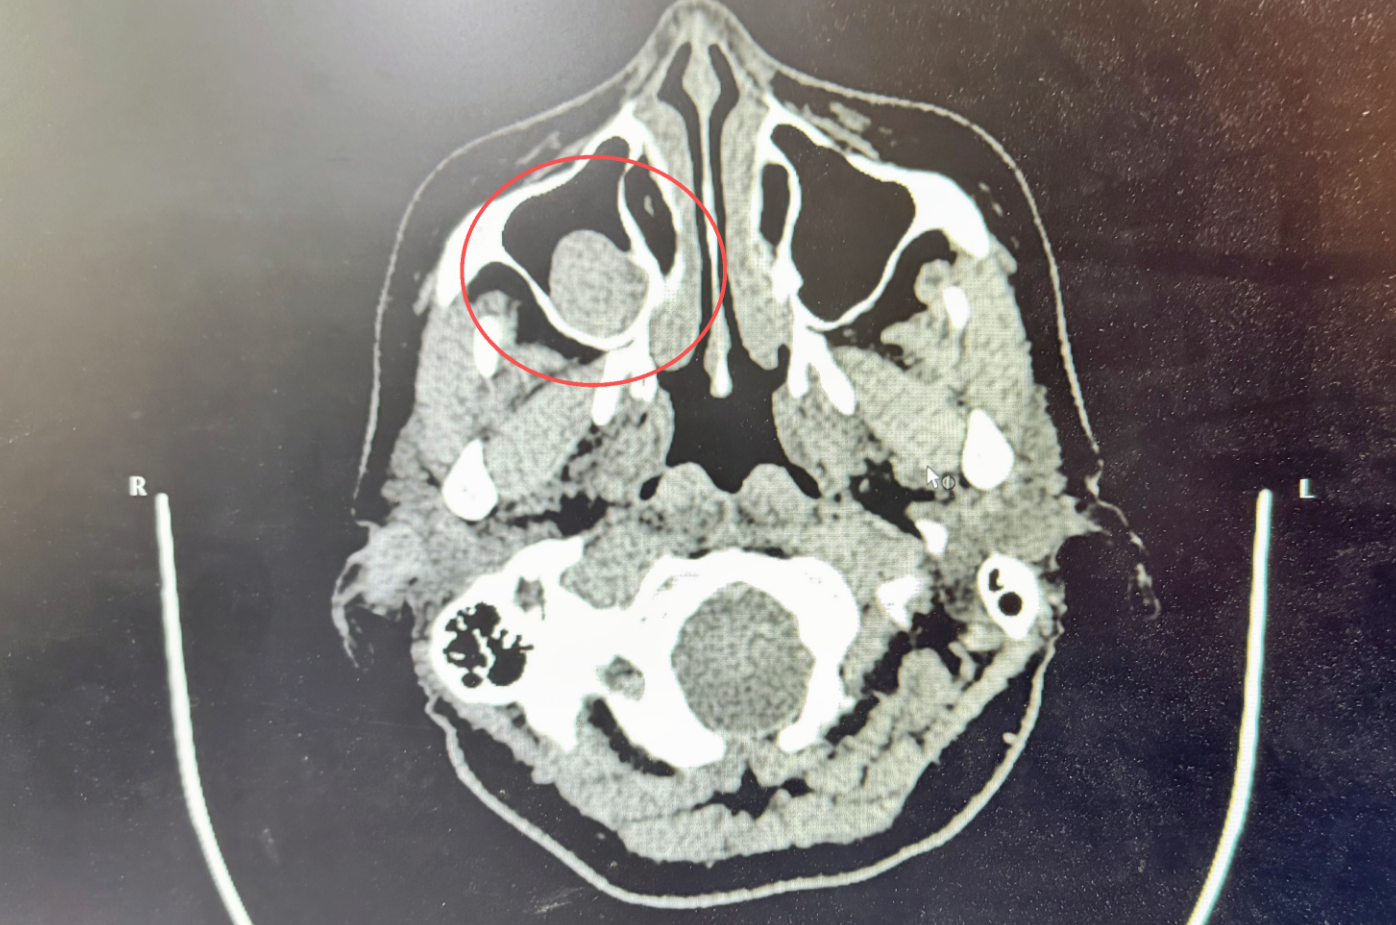

鼻咽镜显示:鼻腔粘膜慢性充血,双侧下鼻甲粘膜糜烂并见血痂附着,双下鼻甲肥大,鼻中隔不规则偏曲;鼻部CT提示右侧上颌窦囊肿。

上颌窦囊肿作为一种常见的鼻腔良性疾病,早期可能无明显症状,但随着囊肿增大,会引发头面部胀痛、鼻塞、嗅觉减退等不适。而鼻中隔偏曲和肥大性鼻炎则会进一步加重鼻腔通气功能障碍,形成恶性循环。